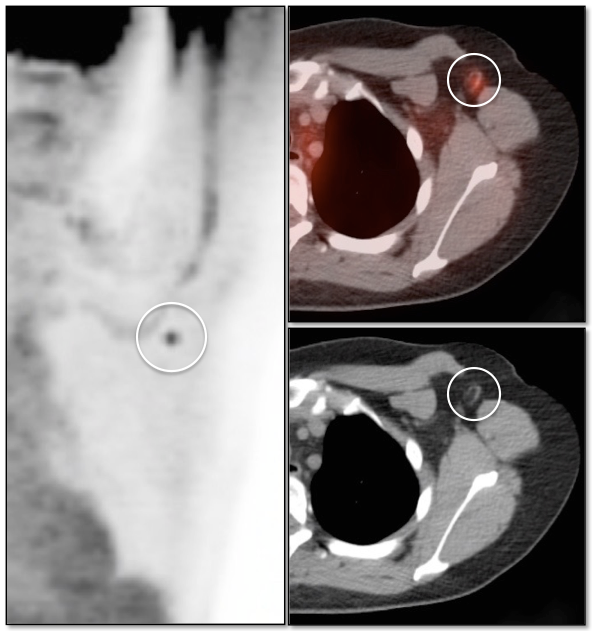

Extravasation of Injected FDG

FDG is injected intravenously. As many cancer patients have challenging venous access issues, partial extravasation of FDG during injection is not uncommon (an estimated 10% of patients have evidence of extravasation on their PET images).

Extravasation of FDG at the time of the intravenous injection can result in false positive interpretations due to:

- Focal intense uptake at the injection site.

- Linear uptake along the lymphatic channels within the arm (appearing as long vessels).

- Focal uptake in small ipsilateral axillary nodes.

If these nodes are enlarged, be cautious before dismissing them as “injection-related”. We have seen more than one case of a radiologist calling axillary nodes “injection-related”, when the patient was injected in the opposite arm.